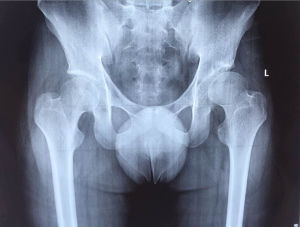

(1)髖關節發育不良:又稱為髖關節不穩定,X線片常以髖臼指數增大為特點,多數採用髖關節外展位而隨之自愈,約1/10將來發展為先天性髖脫位,還有少數病例持續存在髖臼發育不良,年長後出現症狀。

(2)髖關節半脫位:X線片有髖臼指數增大,髖臼覆蓋著部分股骨頭,這是一種獨立的類型,可長期存在而不轉化為全脫位。

(3)髖關節全脫位:股骨頭完全脫出髖臼,根據股肌頭脫位的高低可分為四度:

Ⅰ度:股骨頭僅向外方移位,位於髖臼同一水平;

Ⅱ度:股骨頭向外、上方移位,相當於髖臼外上方水平;

Ⅲ脫出的股骨頭位於髂骨翼的部位;

Ⅳ脫出的股骨頭上移達骶髂關節水平。

骨盆平片:髖臼指數正常為20-25°,至12歲時基本恆定於15°,異常為>30°;

髖臼指數

CE角:正常值4歲+15°以上,15歲為+20°以上

Sharp角:該角>40°即表示髖臼發育不良。

股骨頸前傾角的測量:X線雙平片

頭臼指數(AHI):由股骨頭內緣到髖臼外緣的距離A比股骨頭的橫徑B,表示股骨頭的大小與髖臼深度不相稱的狀態。其特點是隨年齡的增長而頭臼指數隨之下降,一般正常值在84-85左右。其計算公式為AHI=A/B×100。

髖關節間隙:與正常側相比較,雙側患者與同年齡髖關節進行比較。測定股骨頭最高點的面與髖臼軟骨底面的距離,分為5級,4級為正常間隙,3級較正常窄1/4,2級較正常窄1/2,1級較正常窄3/4,0級關節間隙完全消失。用以判斷有無創傷性關節炎的標準。